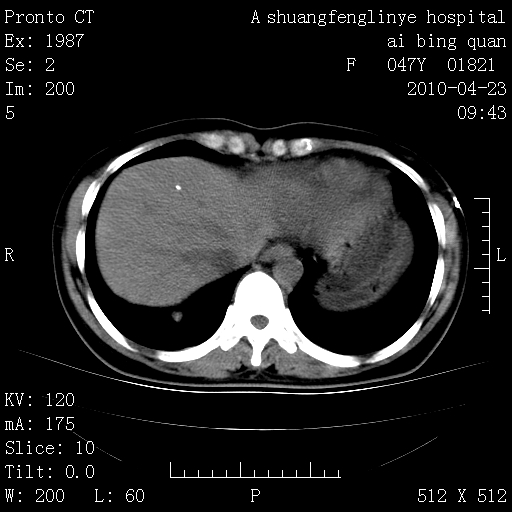

标题: CT25944:胸痛、气短、前几日高烧!肺Ca?请会诊! [打印本页]

标题: CT25944:胸痛、气短、前几日高烧!肺Ca?请会诊!

kaolv 周围型肺癌并同肺转移

双肺多发结节,考虑转移瘤,肺癌肺转移不除外

周围型肺癌并肺转移